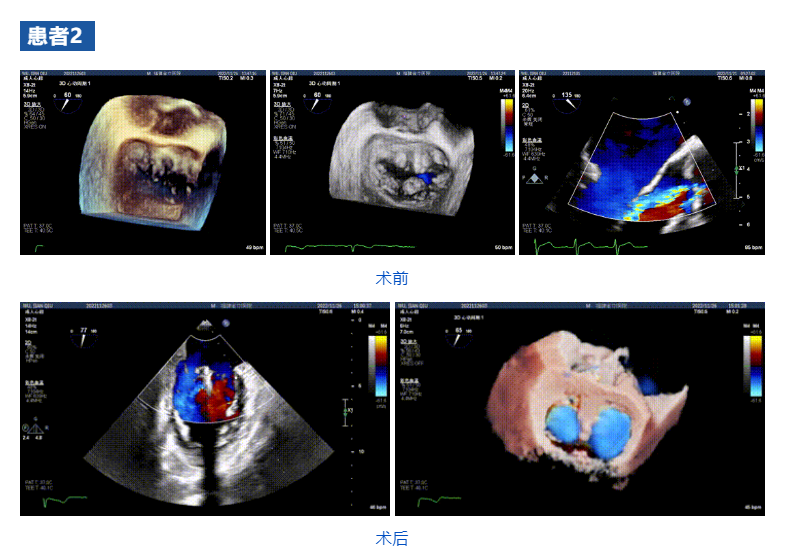

接受治療的三例患者均為器質(zhì)性重度二尖瓣反流(DMR)患者,術(shù)前超聲提示二尖瓣后葉脫垂伴4+反流,左室舒張功能減退。郭延松教授攜同團(tuán)隊成員陳新敬副教授和洪景宣、方明程、楊清勇主治醫(yī)師、心外科丁杭主任以及超聲科賴寶春、葉振盛主治醫(yī)師共同進(jìn)行病情討論??紤]到患者高齡、基礎(chǔ)疾病多、STS評分高,為外科手術(shù)極高?;颊?,不適合進(jìn)行外科開胸二尖瓣手術(shù),因此決定為患者實施經(jīng)導(dǎo)管緣對緣修復(fù)介入術(shù)(JensClip經(jīng)導(dǎo)管瓣膜夾系統(tǒng))。

在浙江大學(xué)醫(yī)學(xué)院附屬第二醫(yī)院王建安教授團(tuán)隊的支持下,手術(shù)經(jīng)股靜脈-房間隔入路,采用全身麻醉插管,在TEE和DSA引導(dǎo)下完成房間隔穿刺。置入JensClip瓣膜夾系統(tǒng)后,在左房調(diào)整瓣膜夾的位置和軸向,后進(jìn)入左室,在TEE引導(dǎo)下捕捉二尖瓣前后瓣葉,并關(guān)閉瓣膜夾。經(jīng)TEE反復(fù)確認(rèn)手術(shù)效果后最終鎖定并釋放瓣膜夾。術(shù)后即刻超聲顯示瓣膜夾位置穩(wěn)定,功能良好,二尖瓣反流由術(shù)前4+減少至微量,手術(shù)圓滿成功。